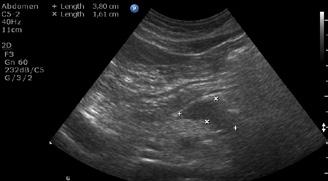

A opera sau a nu opera? Raspunsul ecografistului

Dr. Dan Adrian Stănescu 24